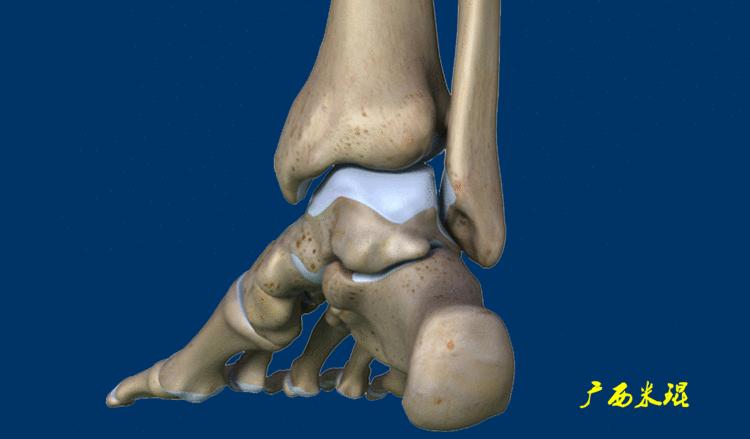

距骨骨软骨损伤(Osteoehondral lesions of the talus, OLT)是指距骨滑车局限性的骨软骨损伤,是累及距骨穹隆关节软骨面和(或)软骨下骨质的损伤,表现为局部关节软骨剥脱,在临床较为常见,损伤后可引起踝关节反复疼痛、肿胀等不适,是踝关节慢性疼痛的主要原因之一。

外伤导致的距骨骨软骨损伤是有一定的规律可循的,前外侧损伤通常是踝关节内翻和背伸*力暴**导致距骨顶的前外侧面撞击腓骨引起的,剪切*力暴**产生切线应力而形成的损伤一般比较浅,接近圆片状。

而后内侧损伤则是由于踝关节内翻、跖屈和外旋*力暴**导致后内侧距骨顶撞击胫骨远端关节面产生相对垂直的*力暴**,从而产生较深的、杯形的损伤。